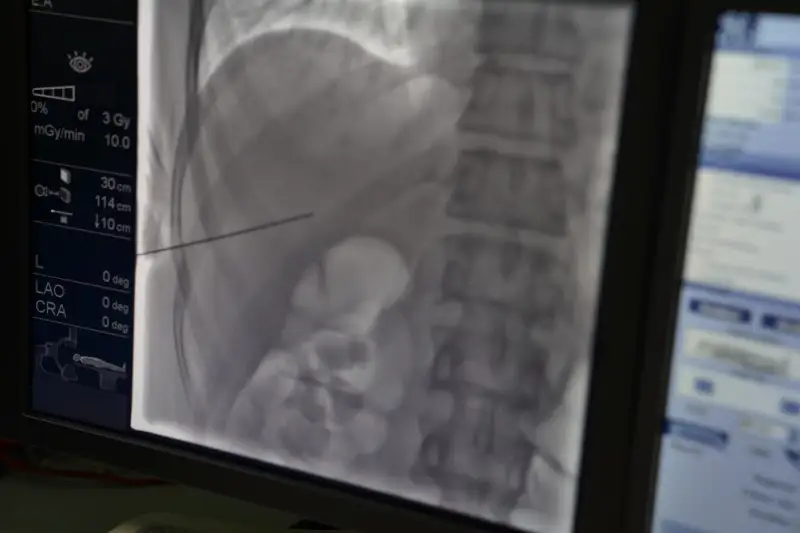

В медицинском центре сообщили, что в больницу были экстренно госпитализированы два пациента, 34 и 36 лет, с циррозом печени, портальной гипертензией с кровотечением из вен пищевода. По жизненным показаниям им срочно требовалась операция. Сложнейшие и высокотехнологичные операции врачи отделения рентген-эндоваскулярной хирургии ВК ОСМЦ в Усть-Каменогорске проводили совместно с коллегами из госпиталя при Медицинском университете города Семей. Кроме того, за работой коллег наблюдали более 20 хирургов из других медорганизаций области.

«Эти пациенты ожидают трансплантацию печени. Хотя данная процедура не лечит цирроз печени, но для больных с таким страшным недугом TIPS (трансяремное внутрипеченочное портокавальное шунтирование) — это способ продлить жизнь и дождаться трансплантации. Благодаря обучению мы поставили данную операцию в ряд вполне обыденных, доступных для жителей ВКО, тем самым продлевая жизни наших пациентов. Этот случай как раз показал, что мы готовы к такому уже сейчас», - рассказал интервенционный хирург ВК ОСМЦ Жандос Уап.

TIPS проводится через небольшой прокол в области шеи. Это одна из самых высокотехнологичных, эффективных эндоваскулярных операций. В областном центре выполнение этой сложнейшей операции ранее самостоятельно не проводилось.